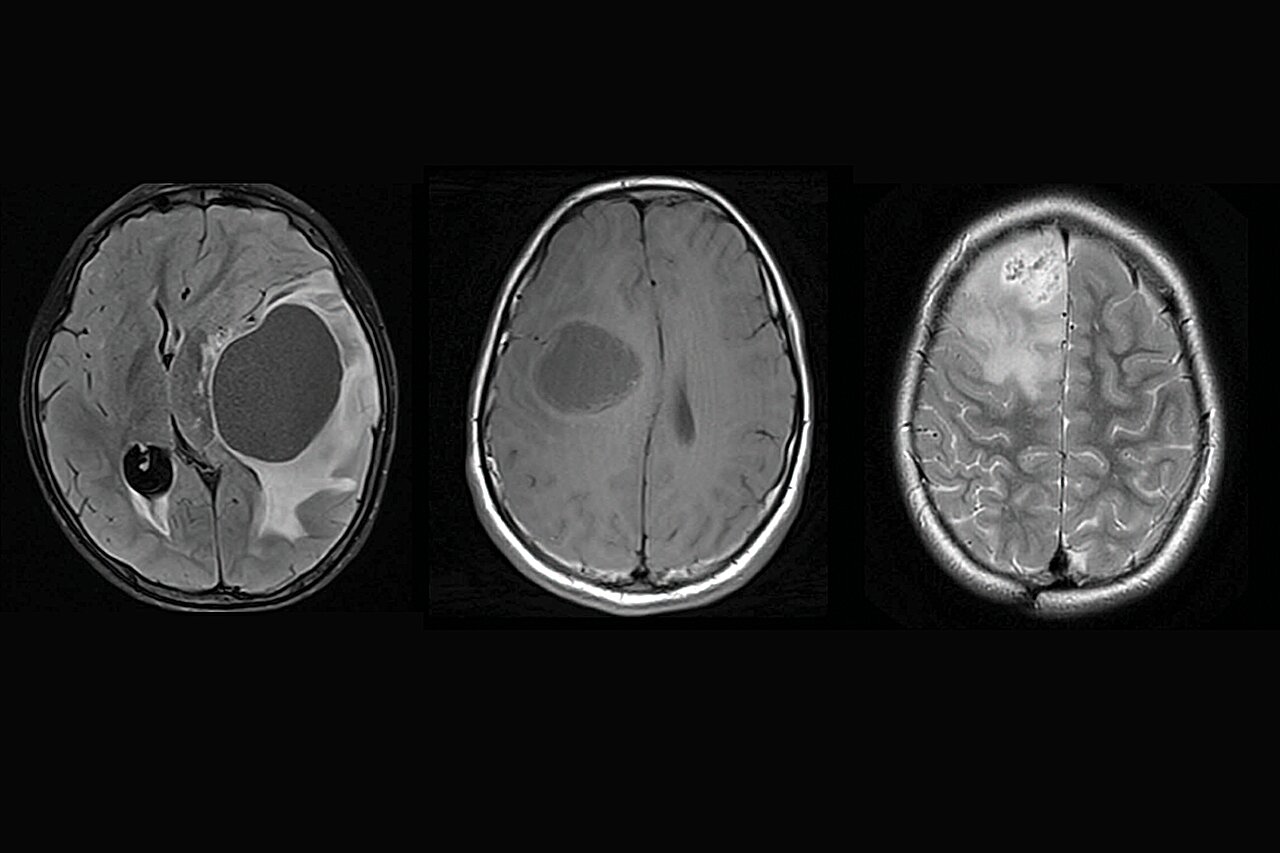

Діагностика гліоми базується на поєднанні клінічного огляду, нейровізуалізації та морфологічного підтвердження пухлини. Основною метою обстеження є визначення локалізації гліоми, її розмірів, ступеня поширення та біологічних особливостей.

Методом вибору для діагностики гліоми є магнітно-резонансна томографія головного мозку. МРТ дозволяє детально оцінити структуру мозкових тканин, визначити межі пухлини та виявити ознаки інфільтрації навколишніх структур.

Комп’ютерна томографія може використовуватися як додатковий метод обстеження, особливо у невідкладних ситуаціях. КТ дозволяє швидко виявити об’ємне утворення мозку та оцінити наявність набряку або зміщення мозкових структур.

Остаточне підтвердження типу гліоми здійснюється за допомогою гістологічного дослідження пухлинної тканини. Морфологічний аналіз дозволяє визначити тип клітин, ступінь злоякісності пухлини та молекулярні особливості гліоми.

Диференційна діагностика гліоми проводиться з іншими внутрішньочерепними пухлинами, метастатичними ураженнями мозку та деякими запальними процесами. Точне встановлення діагнозу є ключовим фактором для вибору правильної тактики лікування.